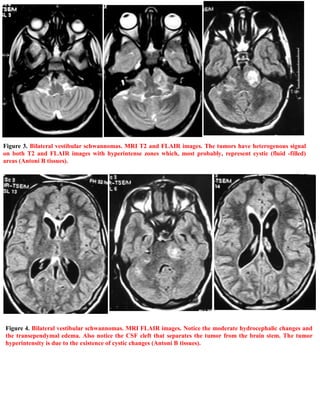

This document is a short case publication from April 2008 edited by Professor Yasser Metwally about a 22-year-old male patient. The patient presented with several neurological symptoms including bilateral tinnitus, headache, hearing loss, eye issues, and mobility issues. The diagnosis was neurofibromatosis type 2 based on MRI scans showing bilateral vestibular schwannomas (tumors on the eighth cranial nerves). The addendum provides information on accessing current and past versions of this case publication online.